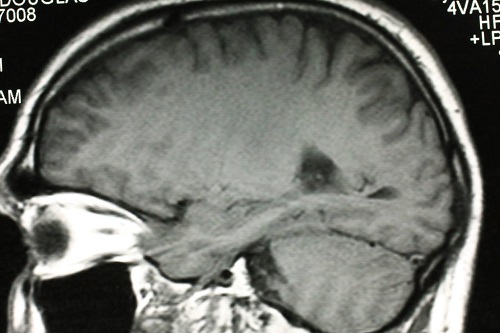

Thuốc chống sốt rét làm tăng điều trị glioblastoma

Thuốc, được gọi là lumefantrine, có thể cải thiện tỷ lệ thành công của phương pháp điều trị bằng xạ trị và hóa trị cho một loại ung thư não nghiêm trọng.

Glioblastoma multiforme (GBM) là một dạng ung thư đặc biệt tích cực, khó điều trị.